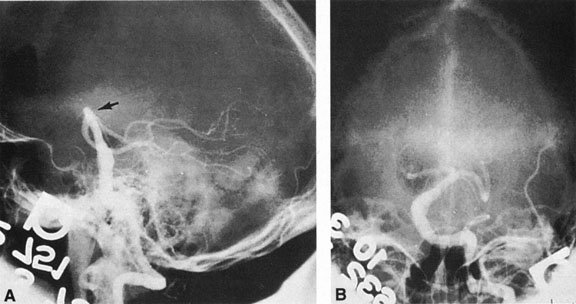

The therapy for AVMs has been reviewed elsewhere.91–93 The preferred treatment remains complete surgical excision of the malformation. However, significant advances in endovascular and radiosurgical techniques have resulted in a marked increase in the use of multimodal, staged approaches to AVM treatment. A variety of intravascular techniques use embolization91 with materials such as particles of polyvinyl alcohol (PVA), platinum coils, and injection of liquid N-butyl-cyanoacrylate (NBCA) adhesive (Fig. 11). Complications of intravascular embolotherapy include vessel perforation by the catheter, migration of embolic materials, and infarction and hemorrhage of normal brain.

Fig. 11. Embolization of middle cerebral vessels that supply occipital lobe arteriovenous malformation (AVM). The patient had a subarachnoid and intraparenchymal hemorrhage that produced a left homonymous field defect. A: Right carotid arteriogram demonstrates contribution via posterior communicating artery to a right occipital lobe AVM. B: Vertebral injection. The arrow points to the enlarged right posterior cerebral artery that is a major feeder of the AVM. C: Right carotid arteriogram during glue embolization procedure. The arrow points to a catheter as it traverses the segment seen in (B). The catheter was advanced via the internal carotid artery but is positioned far posteriorly. D: Upper branches to the AVM now are occluded, with residual low-flow vascularization via the middle cerebral artery. E: Skull film showing radiopaque glue within the AVM and blood vessels previously supplying it. The patient had a persistent visual field defect but greatly reduced headache and no persistence of subjective bruit. (Courtesy of Dr. Joseph Horton.)